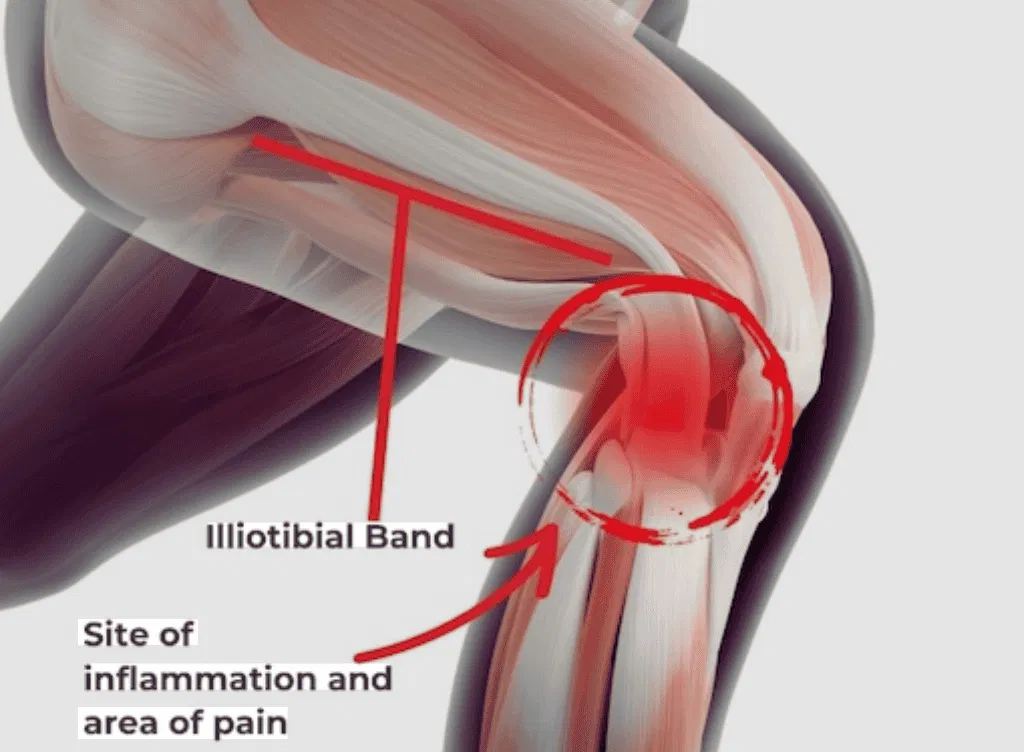

Biomechanical contributors include hip abductor weakness, which alters lower limb alignment and increases lateral knee stress (a primary driver of ITBS and PFPS); quadriceps weakness or inhibition, which raises patellofemoral joint loading; poor ankle dorsiflexion, which alters running mechanics proximally; and foot pronation or supination patterns that affect tibial rotation and knee tracking.

Iliotibial Band Syndrome: Sharp or burning pain on the outer aspect of the knee, characteristically appearing at a consistent point during a run — often around the 2–3 km mark — and easing with rest. May be accompanied by localised tenderness over the lateral femoral epicondyle.

Corticosteroid injections to rapidly reduce inflammation and pain. This is particularly useful in conditions such as pes anserine bursitis or acute ITBS, creating a window of reduced pain in which rehabilitation can progress more effectively.